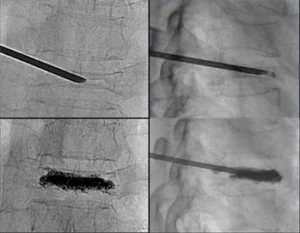

Le fratture vertebrali, se non trattate correttamente, possono portare a gravi complicazioni come dolore cronico, perdita di mobilità, e in alcuni casi, danni permanenti ai nervi. È quindi fondamentale un intervento tempestivo e mirato per ridurre il dolore e favorire la guarigione. I trattamenti per le fratture vertebrali possono includere radiologia interventistica, tecniche minimamente invasive come la vertebroplastica o la kyphoplastica, che permettono di ripristinare la stabilità della vertebra senza ricorrere a interventi chirurgici tradizionali. Queste tecniche vengono eseguite sotto guida radiologica, garantendo alta precisione e riducendo i rischi per il paziente.